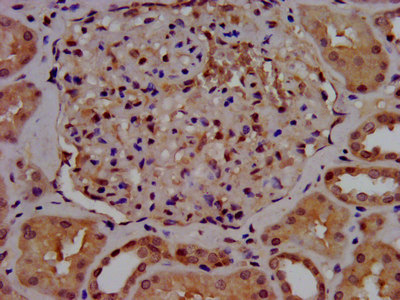

IHC image of CSB-PA021709LA01HU diluted at 1:500 and staining in paraffin-embedded human kidney tissue performed on a Leica BondTM system. After dewaxing and hydration, antigen retrieval was mediated by high pressure in a citrate buffer (pH 6.0). Section was blocked with 10% normal goat serum 30min at RT. Then primary antibody (1% BSA) was incubated at 4°C overnight. The primary is detected by a biotinylated secondary antibody and visualized using an HRP conjugated SP system.